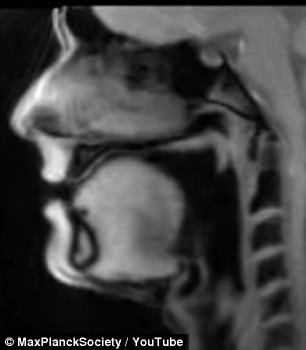

简单来说,该系统能够将MRI扫描结果从静态图片转化为视频动图,首次让人们看到“心脏跳动、关节移动”的3D视频,或者吞咽和说话时喉部的运动过程。

“有史以来第一次,我们能够直接观察关节的运动、说话时喉部的动作、吞咽的过程、心脏的跳动、下巴的闭合等等,从而更好地研究病人为何会在膝盖弯曲时感到疼痛,或者出现烧心、口吃、胸部疼痛等症状。”

在一段视频中,我们可以看到心脏在胸腔中跳动的过程。而在另一段令人略感惊悚的视频中,一名男子正在说德语,同时舌头上固定着一枚微型摄像头。从视频中可以看出,当嘴唇与喉部运动发声时,舌头也会随之动个不停。此外还有一段比较搞笑的视频,拍下了某人唱歌时口腔内部的运动情况。